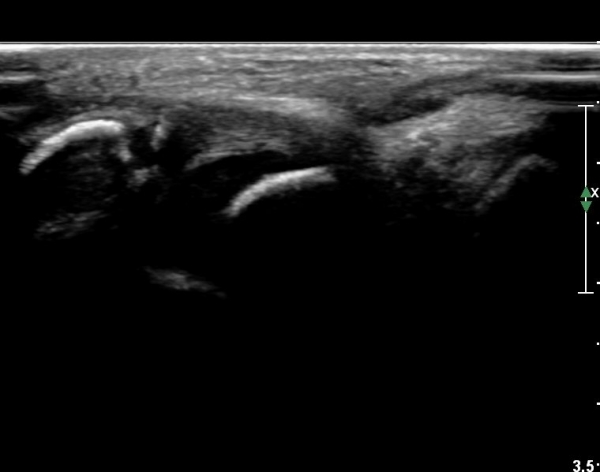

Àü°ÅºñÀÎ´ë ºÎÀ§ ±¹¼ÒÀû ¾ÐÅë, ºÎÁ¾À» º¸ÀÓ. Àü¹æ´ç±è°Ë»ç (+)

ÃÊÀ½ÆÄ °Ë»ç